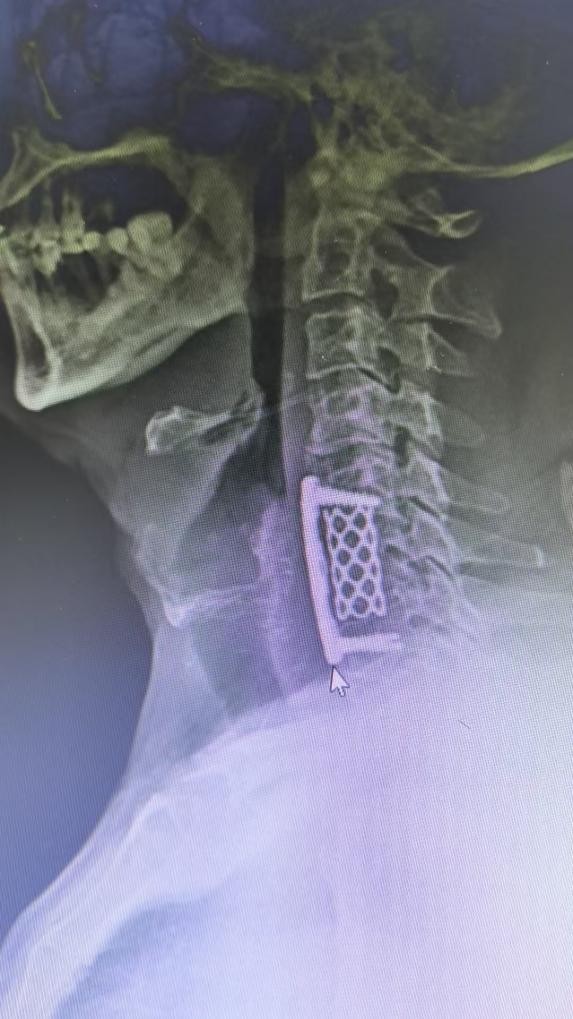

经过充分的术前准备和多学科讨论,脊柱科团队为患者制定了缜密的手术方案。手术当天,麻醉后患者仰卧头过伸,借导航与 C 臂机定位颈 5 - 7 区域,颈前右侧切 5cm 口,依次切开组织并妥善牵开,显露出关键结构且避伤血管神经等。关键步骤咬除 C6 椎体,摘除 C5/6、C6/7 椎间盘减压,再选钛网植骨,放钢板用螺钉固定,恢复椎间隙高度与颈椎稳定,助力患者康复。

整个手术过程顺利,术中出血约 80ml,患者生命体征平稳,无不良反应。术后,在医护人员的悉心照料下,患者恢复良好。其右上肢疼痛及手指麻木症状明显减轻,进食正常,睡眠质量也得到了显著改善,不再受病痛的困扰,对治疗效果非常满意。